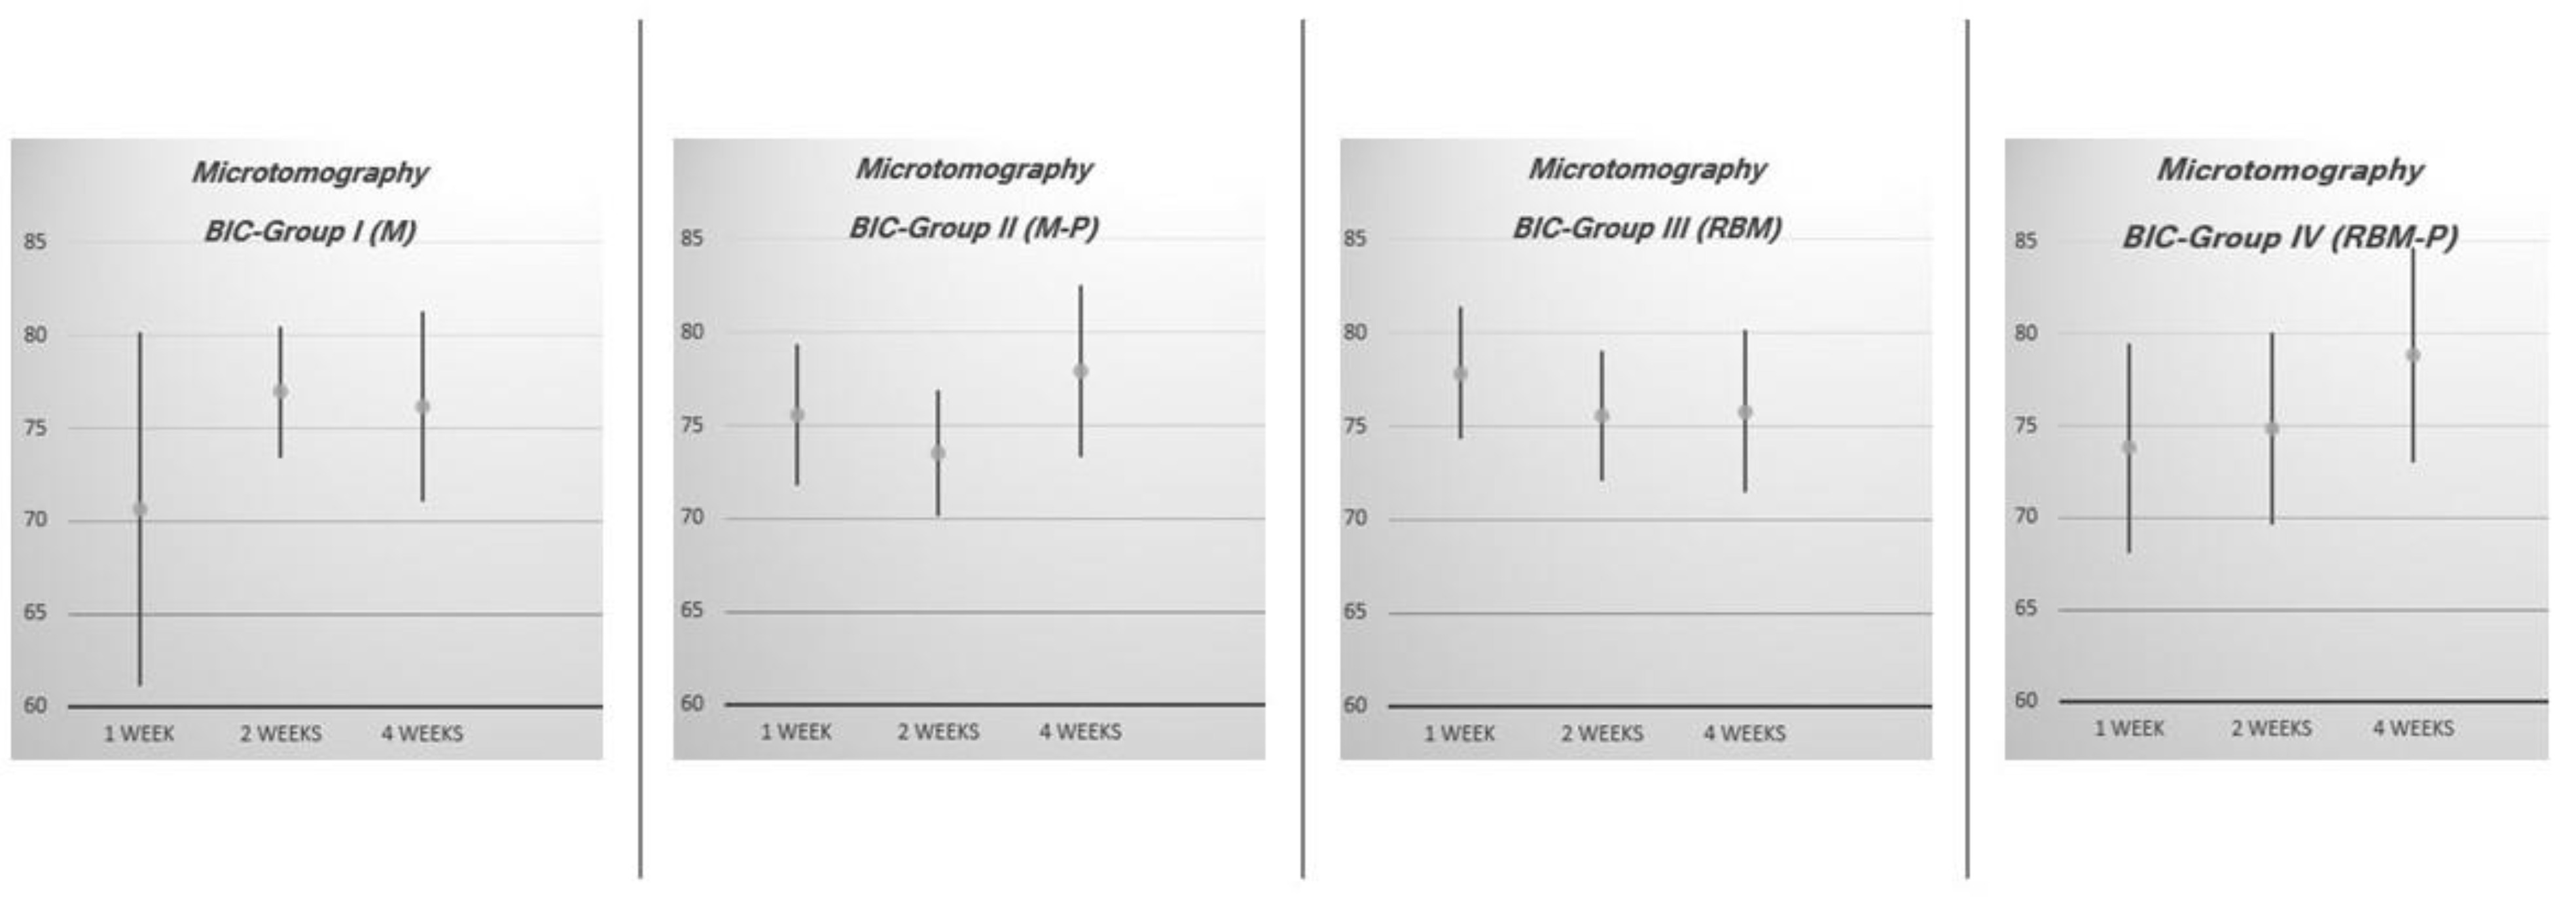

| Experimental Group | n | 1 Week | 2 Weeks | 4 Weeks | |||

|---|---|---|---|---|---|---|---|

| BIC (%) | C.I. 95% | BIC (%) | C.I. 95% | BIC (%) | C.I. 95% | ||

| I (M) | 12 | 70.67 | 61.09–80.25 | 76.97 | 73.42–80.52 | 76.16 | 71.05–81.27 |

| II (M-P) | 12 | 75.52 | 71.73–79.31 | 73.48 | 70.09–76.87 | 77.92 | 73.34–82.50 |

| III (RBM) | 12 | 77.85 | 74.38–81.38 | 75.60 | 72.11–79.09 | 75.81 | 71.48–80.14 |

| IV (RBM-P) | 12 | 73.78 | 68.13–79.43 | 74.83 | 69.61–80.05 | 78.80 | 72.95–84.65 |